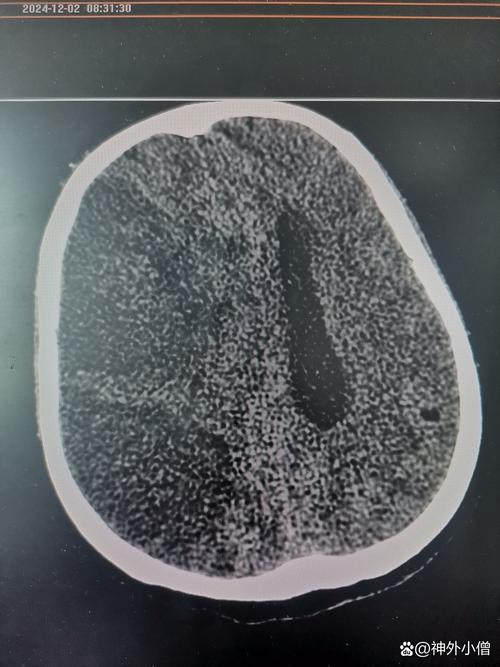

- 影像学检查(金标准):

- 头颅CT平扫: 可在早期排除脑出血,但发病6小时内可能看不到明显的梗死灶,仅见早期脑水肿的征象(脑沟变浅、脑室受压)。

- 头颅MRI(DWI序列): 是诊断早期脑梗最敏感、最准确的方法。 发病后几十分钟甚至几分钟就能发现缺血病灶。